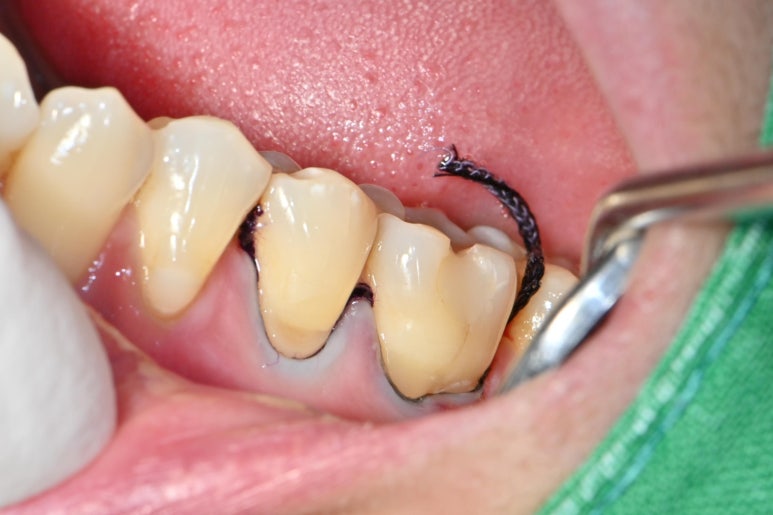

다음 사진으로 어떤식으로 치료하는지 보여드리겠습니다.

먼저 치아 표면을 깨끗하게 정리합니다.

스케일러나 표면 연마제등을 이용하여

남은 치석이나 치태를 깨끗하게 정리합니다.

그후에 사진에 보이는 검정 실인 징지코드를 넣습니다.

징지코드는 잇몸 하방에서 올라오는 삼출물이나

혈액을 억제하는 효과가 있습니다.

그리고 혀 안쪽으로 솜을 넣어서

침이 넘어 오지 않게 철저하게 방습을 합니다.